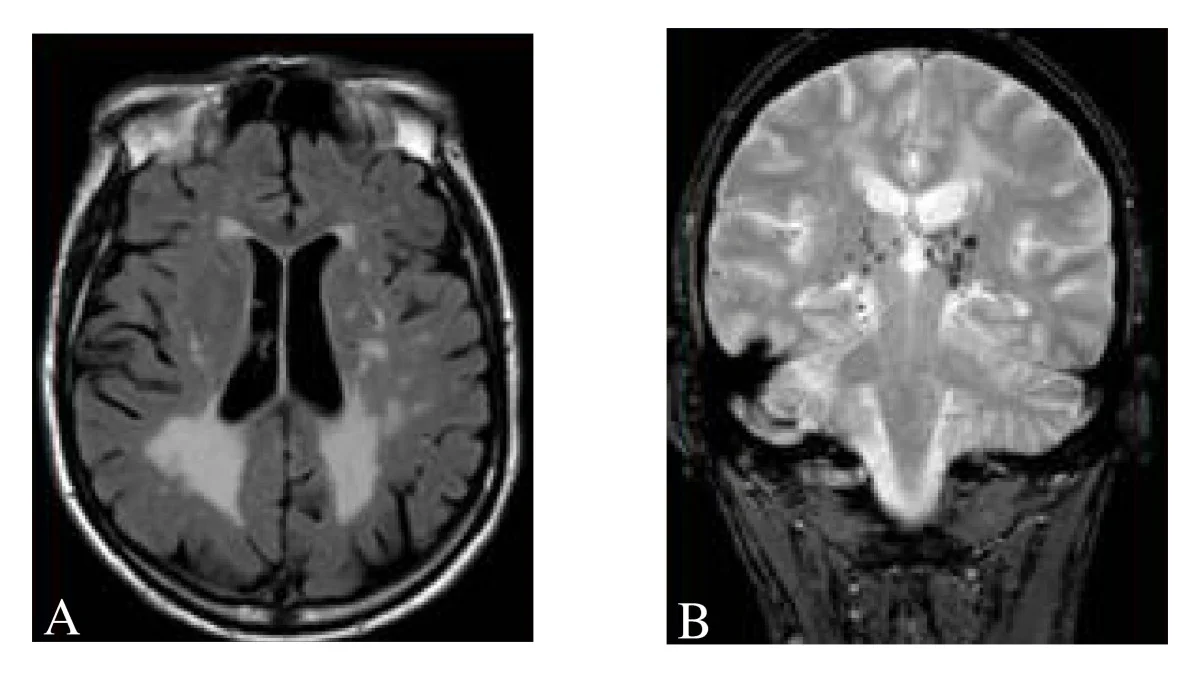

Detecting Subtle Brain Lesions with Machine Learning